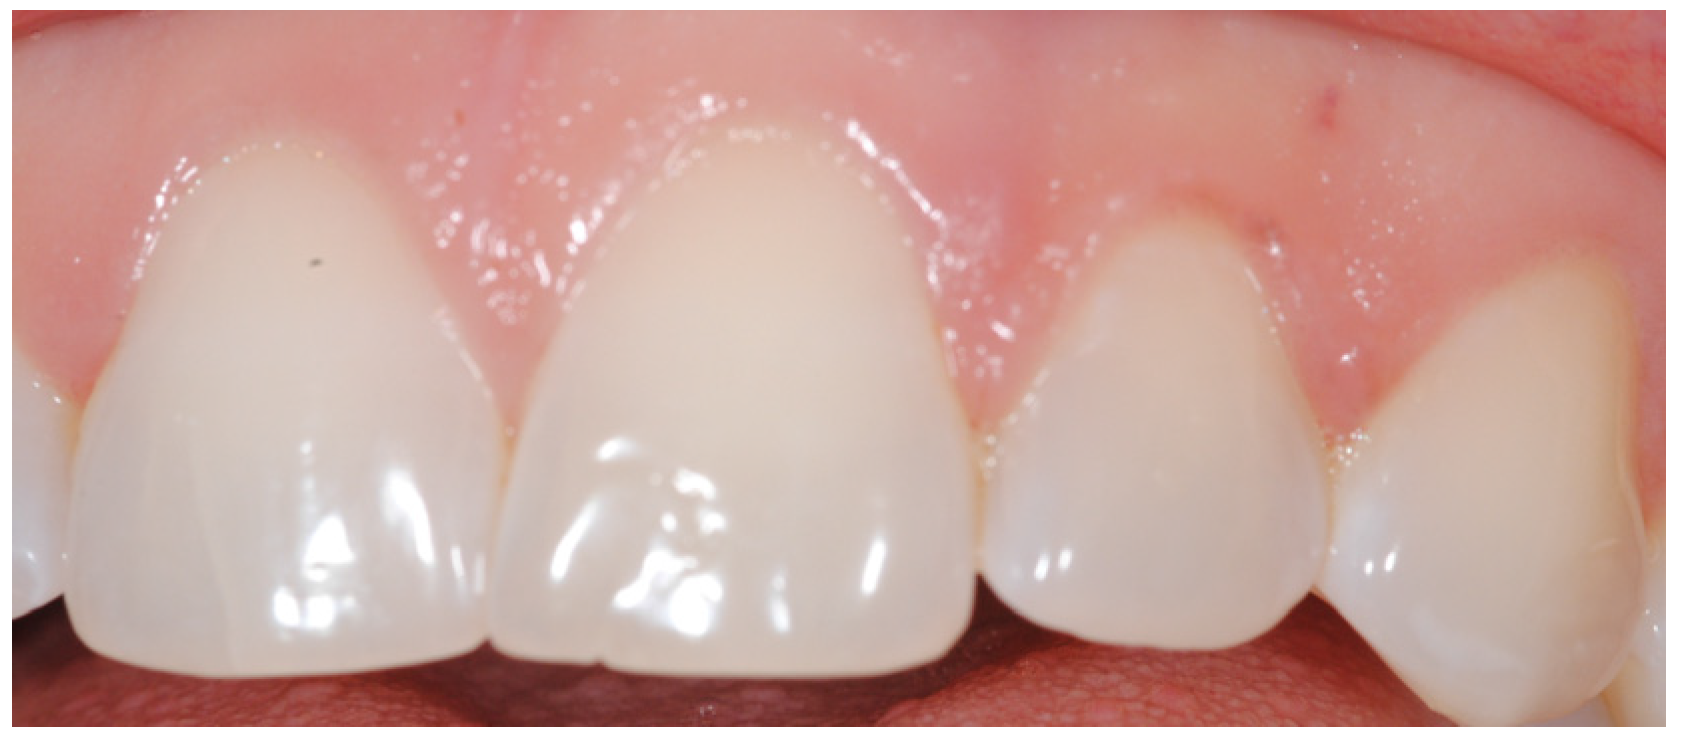

2. Case Presentation